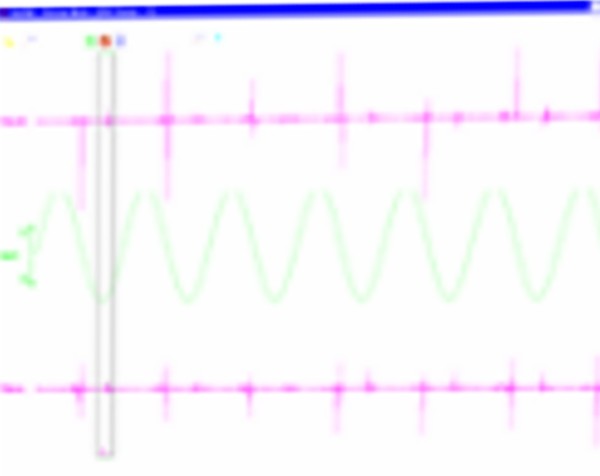

Pre Operatoria Post Operatoria

Pre Operatoria Post Operatoria

Pre Operatoria Post Operatoria

Pre Operatoria Intra Operatoria

Pre Operatorio Post Operatorio